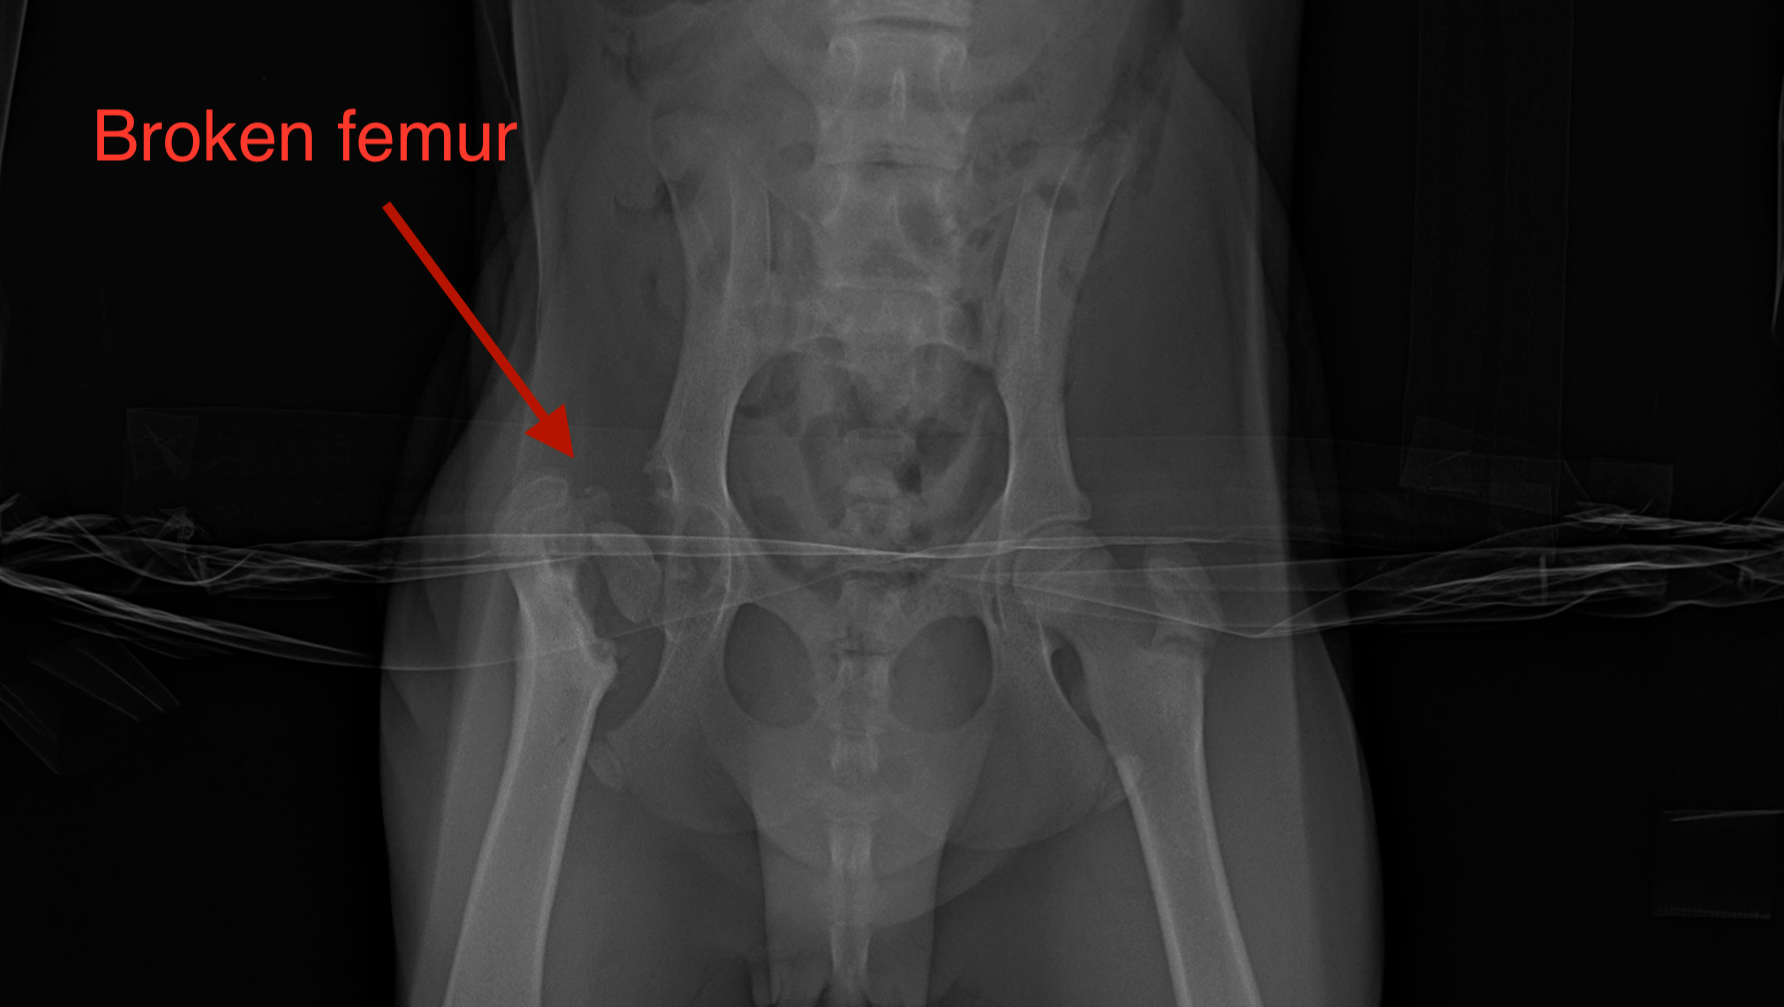

Ducky’s face and head were terribly swollen because of several skull fractures. She could not walk due to a broken hind leg, and badly deformed front limbs (partially a result of nutritional starvation). She had several broken ribs, and fractures throughout her body in different stages of healing (without treatment or medications,) and severe skin infections.

Ducky is on a waitlist to have her hind leg repaired through the amazing FRACTURE program at UC Davis, and we are asking for your generosity to help Ducky receive the very important reconstruction of her front wrists that will allow her to live a long normal life with her forever family!